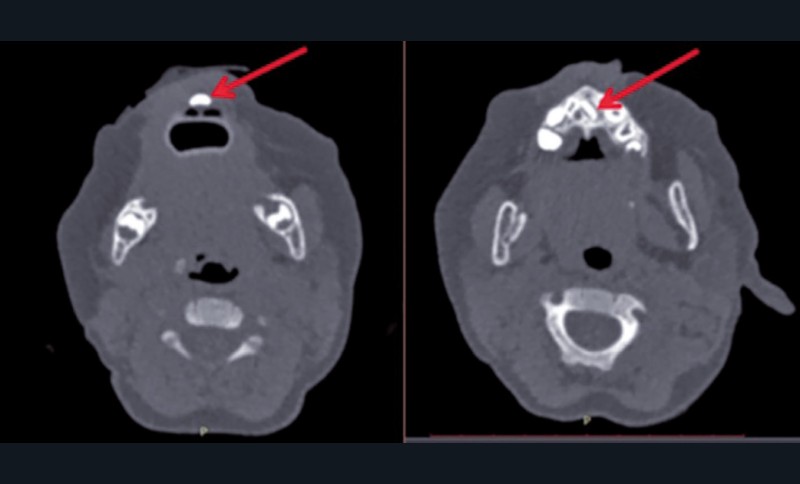

Un scanner, précédemment réalisé à la demande du pédiatre, objective une formation dentaire médiane ainsi que la présence d’un germe unique et médian d’incisive centrale permanente (fig. 3). En outre, il permet d’écarter l’hypothèse d’une fente palatine sous-muqueuse ou d’une sténose des orifices piriformes.